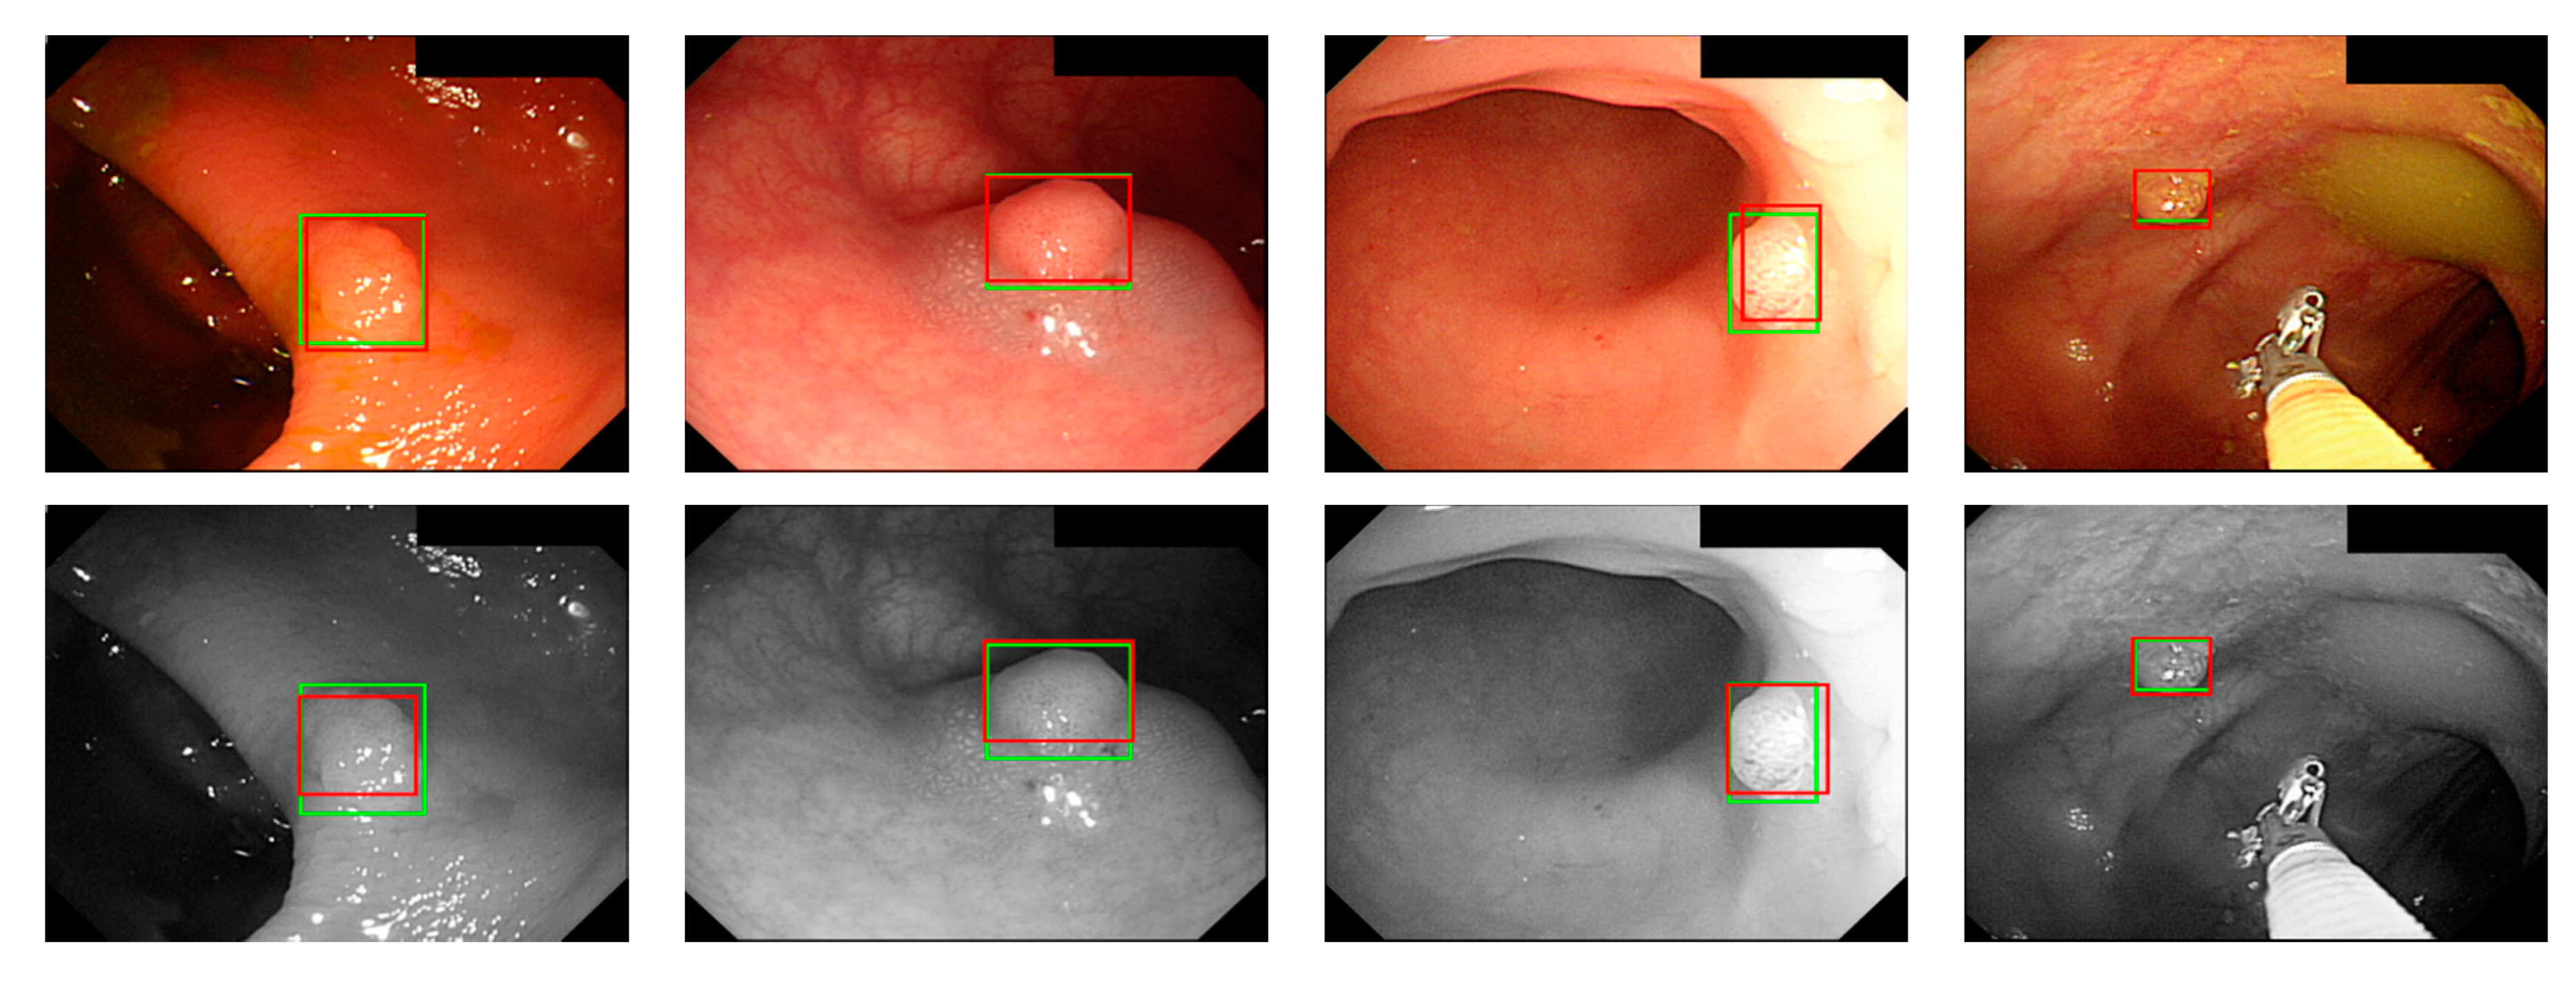

Figure 10.

WL polyp detection.

Figure 11.

NBI polyp detection.

where ai is the input value; p is the pooling regions; n is the pooling size; and aj is the output value after the maximum value is obtained. Polyp detection was then conducted in the bounding box transform layer. The prediction result of the feature map was obtained in the last layer and was output through a 1 × 1 convolutional layer by using a pixel-based approach and converted to a bounding box mode for display [50]. There are eight groups of bounding boxes to locate the polyps: (16, 16), (32, 32), (24, 48), (48, 24), (60, 80), (108, 72), (216, 144), and (180, 180). The cutoff value of polyp detection is 0.2. The size of the predicted bounding box was adjusted by converting it to the range of a true-value bounding box. Table 3 displays the framework of the CNN model. Figure 10 and Figure 11 show the results of WL and NBI polyp detection, respectively, where the first column is the RGB image; the second column is the grayscale image; the red box is the prediction box; and the green box is the actual polyp location marked by the clinician, namely the GT.